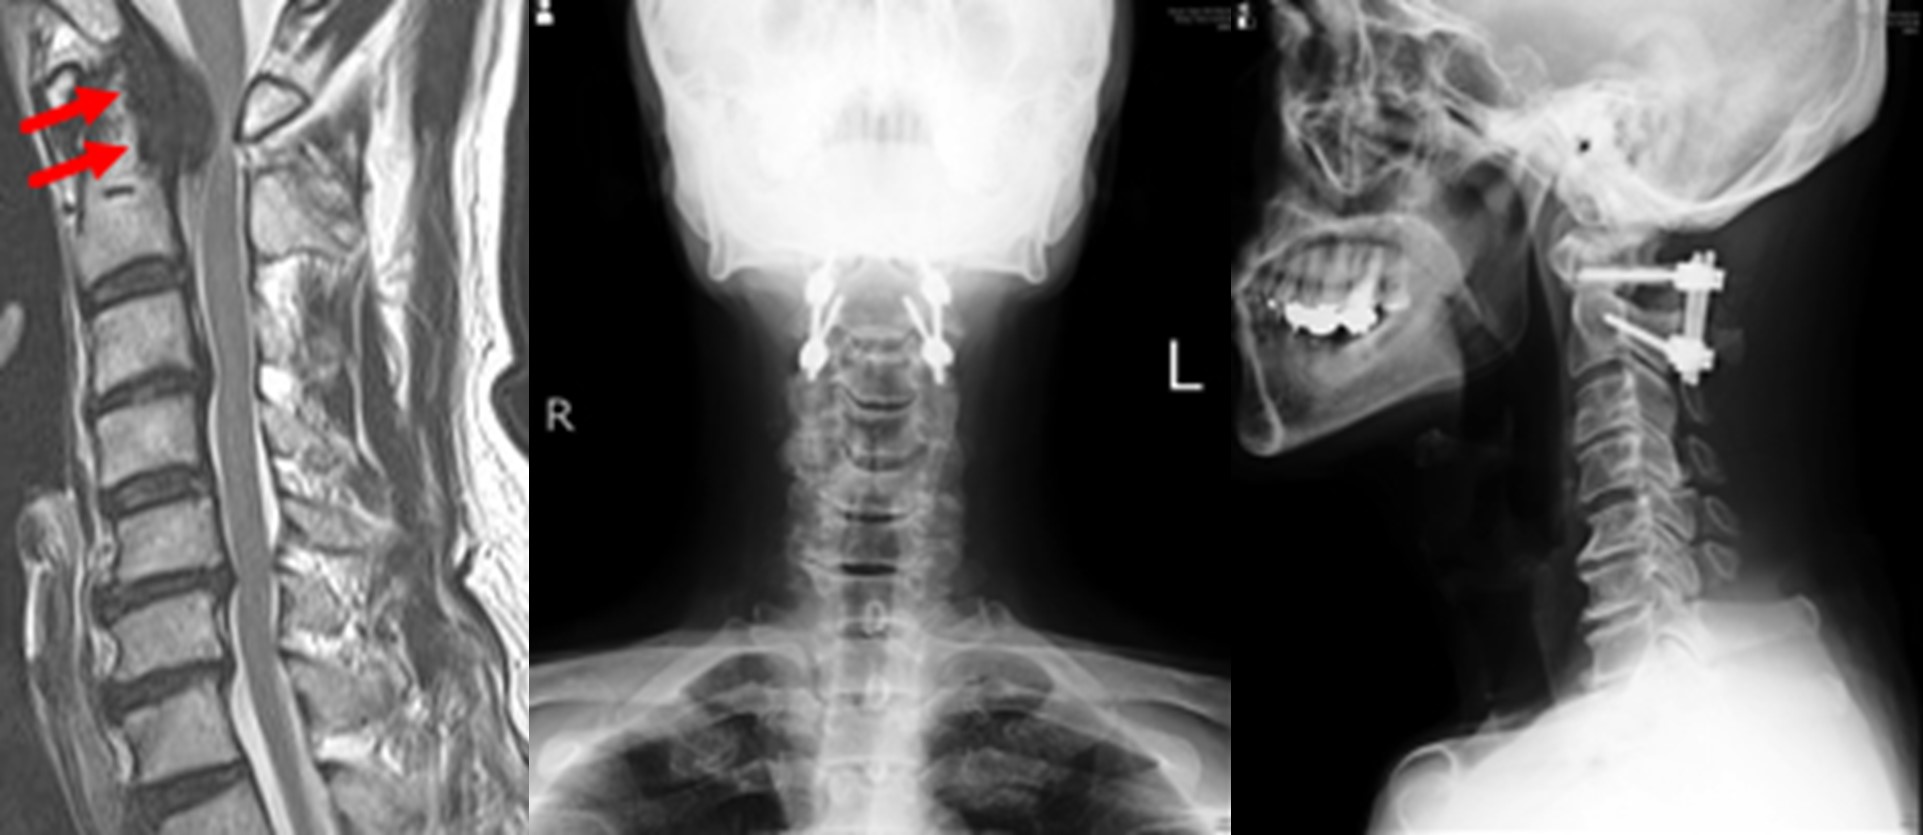

図 第2頚椎(軸椎)歯突起後方偽腫瘍に対する頚椎後方除圧固定術

関節リウマチは四肢の関節だけでなく、脊椎にも様々な障害が生じます。

本症例では、環軸椎という脳に近い首の骨にぐらつきが生じ、2番目の頚椎の後方に偽腫瘍と呼ばれる病変が形成され、脊髄が強く圧迫されていました。金属製のスクリューにより頚椎のぐらつきが固定されると、偽腫瘍は自然縮小し神経症状も改善しました。